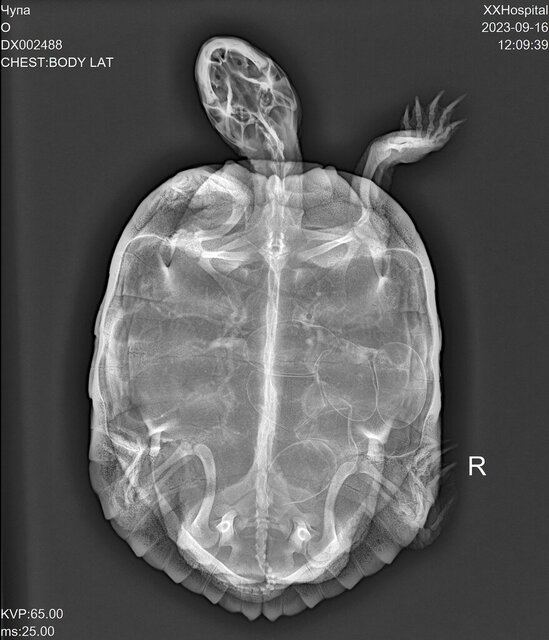

Abc01 Ваше имя: Арина Локация: Россия, Спб Опубликовано: 16 сентября 2023 Опубликовано: 16 сентября 2023 1. Сочи, 22 года. 2. Красноухая черепаха, самка. 3. 50-литровый контейнер, пока нет возможности из-за ремонта купить 100-литровый. 4. Фильтр, уф-лампа (не греющая, просто уф-лампа), термометр. 4.1. Нет лампы накаливания, должна 20 сентября прийти с озона лампа Sera Reptil Sun Heat 100Вт, она и с УФ и греющая, но производитель не пишет, какой именно процент UVB. На сайте черепахи.ру она была в списке рекомендованных, поэтому ее заказала. 4.2. На данным момент стоит только уф-лампа RESUN UVB-10%, стоит с 2 мая, включаю с 9 до 23. 4.3. В качестве берега использую камень, большой, больше 7 кг, черепаха взбирается на него и лежит на нем всем телом под лампой. 4.4. Установлен фильтр внутренний AQUAEL FAN FILTER 1 plus для аквариума 60-100л (320л/ч, 4.7Вт) 4.5. На данный момент обогревателя нет, так как весной вышел из строя и его пришлось выкинуть. Грунта нет. Термометр показывает температуру воды 26 градусов. Температура в комнате такая же, если не выше. Черепаха ест Tetra ReptoMin Sticks, до случившегося ела понемногу каждое утро. Последние 1,5-2 недели давала примерно каждые 3 дня чайную ложку фарша минтая с витаминной добавкой "АВЗ Рептилайф витаминно-минеральная добавка для рептилий, 30 гр" и порошком "Минеральный MIX с кальцием". Как сказал сегодня вет.врач, черепахе примерно 10 лет, вес 1,385 кг. Примерно 3 недели назад черепаха начала очень суетно себя вести, норовила вылезти из контейнера. Уже три недели ходит по комнате и "роет ямки", сначала передними лапками, потом поочерёдно правой и левой задними лапками, потом переползает на другое место и так по новой, целыми днями. Сегодня пошли к ветеринару, сделали рентген. По рентгену 6 яиц, фото прилагаю. Ветеринар сказала, что у черепахи рахит, что очевидно по искривлению на панцире. Мне ее такой отдали в 2020 году, она была уже взрослая и с кривым панцирем. Ветеринар сказал, что панцирь уже не выпрямится никакими препаратами. Также ветеринар сказала, что таз у черепахи узкий, что яйца при откладке могут застрять и черепаха не сможет разродиться. Ветеринар сказала, что, возможно, придется делать операцию. Рекомендация была дать ей попробовать разродиться самой, дать ей дальше перемещаться и искать себе место, но быть готовой к операции и поискать ветеринара, который успешно сможет ее провести. Ветеринар сказала, что не стоит стимулировать черепаху к кладке. Также ветеринар сказала, что пока нужно перестать давать кальций, так как яйца могут закальцинироваться. До приема у врача предлагала черепахе садок с землей, садок с опилками, но они ей не нравились и она из них вылезала. Она часто роет на линолеуме или коврике для фитнеса. Сегодня принесут песок, предложу ей садок с песком, предварительно помыв его. Очень хочу узнать мнение профессионалов по поводу рентгеновских снимков и, если можно, наводку на хорошего в этом вопросе врача, который проводит онлайн-консультации. Также хочу узнать ваше мнение, можно ли как-то еще помочь черепахе разродиться, кроме предложение субстрата? Я нахожусь в Сочи и мне бы хотелось узнать, есть ли у нас специалисты (хотя бы в краснодарском крае), которые могли бы провести эту операцию, в случае, если она будет нужна? Обращались вет.клинику Айболит, врач Аносова Мария Александровна. Никаких препаратов не вводилось.

Консультанты moth Ваше имя: Мария Локация: Москва Опубликовано: 17 сентября 2023 Консультанты Опубликовано: 17 сентября 2023 @Abc01 наш герпетолог ответила, что черепаха должна разродиться сама - яйца стоят хорошо, вопрос только в "замятышах" (яйца неправильной формы), но и они должны нормально выйти, если черепаха активная. Я ей задала ещё пару уточняющих вопросов про стимуляцию и сколько вообще можно ждать - напишу как ответит. 1

Abc01 Ваше имя: Арина Локация: Россия, Спб Опубликовано: 2 ноября 2023 Автор Опубликовано: 2 ноября 2023 Не знаю, может, эта хроника по поводу действий над черепахой на сносях будет кому-то интересна. Связалась с Татьяной из Беларуси, получила консультацию. Она сказала, что кальций нужно давать, так как яйца все равно будут кальцинироваться, просто черепаха будет черпать этот кальций не из еды, а из своего организма, грубо говоря, из своих костей. Татьяна заметила, что по рентгену не видит рахит, что кости хорошей контрастности. Т.е. в детстве он был, если судить из кривизны панциря, но сейчас все с кальцием хорошо. Назначили бороглюканат кальция после второго рентгена (рентген не был пока сделан, кальций еще не был принят на данный момент). Показала фото, как колоть. Сказала снизить температуру с 26 на 24 градуса, чтобы черепаший гормональный фон снизился, а то она так потенциально может постоянно культивировать в себе яйца, думая, что все условия для этого есть (типа тепло, хорошо, самое время сносить яйца). Уже второй специалист подтвердил, что она должна сама снестись, что никаких физиологических проблем не должно быть. Консультация была 9 октября. Татьяна сказала, что выглядеть все будет следующим образом: вода в садке станет белесой, мутной, что на это нужно обратить внимание, так как это будет признаком кладки, яйца черепаха может моментально съесть после этого. По хронике: спустя несколько дней после консультации поставила новую лампу Sera Reptil Sun Heat 100Вт. Чупа стала с огромным удовольствием под ней греться, буквально не сходила с камня-островка. Лампа помимо УФ-излучения еще и греющая. Пока не было денежной возможности сделать рентген, а пока не сделан рентген нельзя стимулировать кальцием, поэтому единственным изменением стало появление новой УФ-лампы с греющей функцией. 28 октября я проснулась и увидела перед собой активную Чупу, плавающую в мутной белесой воде, были видны какие-то белые кусочки. Я вспомнила, что воду меняла вчера, что фильтр работает, и что меня должна была встретить Чупа в чистой водичке и никак иначе. Сразу подлетела с кровати к садку. Все в точности, как описывала врач. На момент находки в садке были уже множество фрагментов скорлупы и кусочков яиц. Лишь одно уцелело, уплыв за камень-островок. Яйца и правда с мягкой скорлупой. Очень довольна. С зарплаты пойду делать рентген, чтобы посмотреть, что осталось или, не дай бог, прибавилось. Единственное, не знаю, как технически сделать температуру воды в садке ниже. Яйцо Это какое-то из замятых яиц, которое видно на рентгене, не смогла понять, какое именно.